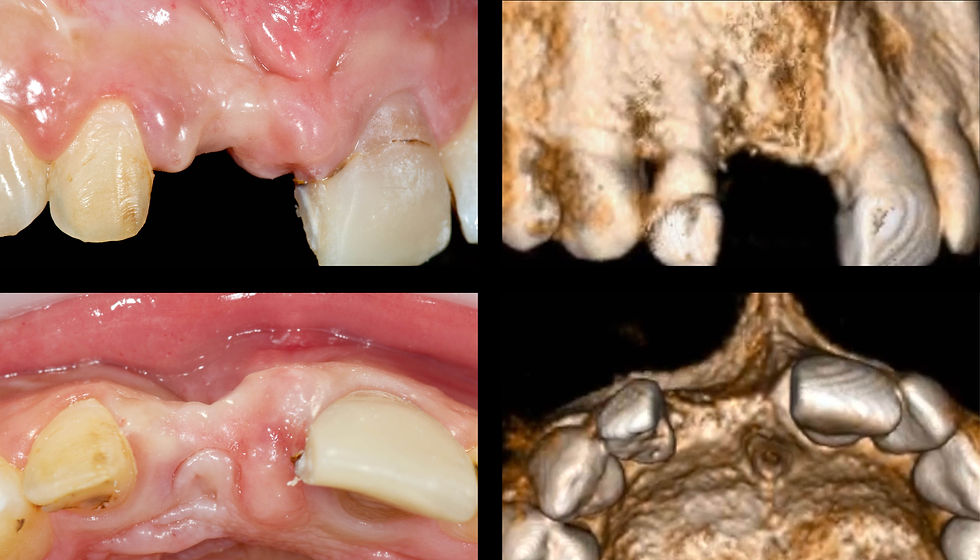

The comparison between the intraoral pictures and the bone volumes revealed at the CBCT examination highlights the severe vestibular bone atrophy and the irregularity of the marginal crest.

The poor vestibular bone thickness and the need to minimize surgical invasiveness lead to opt in favor of guided surgery to insert a Prama RF implant. The choice to leave the palatal portion of the intramucosal neck in contact with the soft tissues is due to the desire to preserve as much as possible the thickness of the residual vestibular bone wall, so as to guarantee a good vascularization to the tissue that will cover it.

Surgical template positioning on the opened flap, for better soft tissue management.

Prama RF implant in place. The convergent neck allows the ability to manage the irregular residual bone levels and the surrounding soft tissues, avoiding “bone augmentation” and leaving room for the clot which will turn into new gingiva.